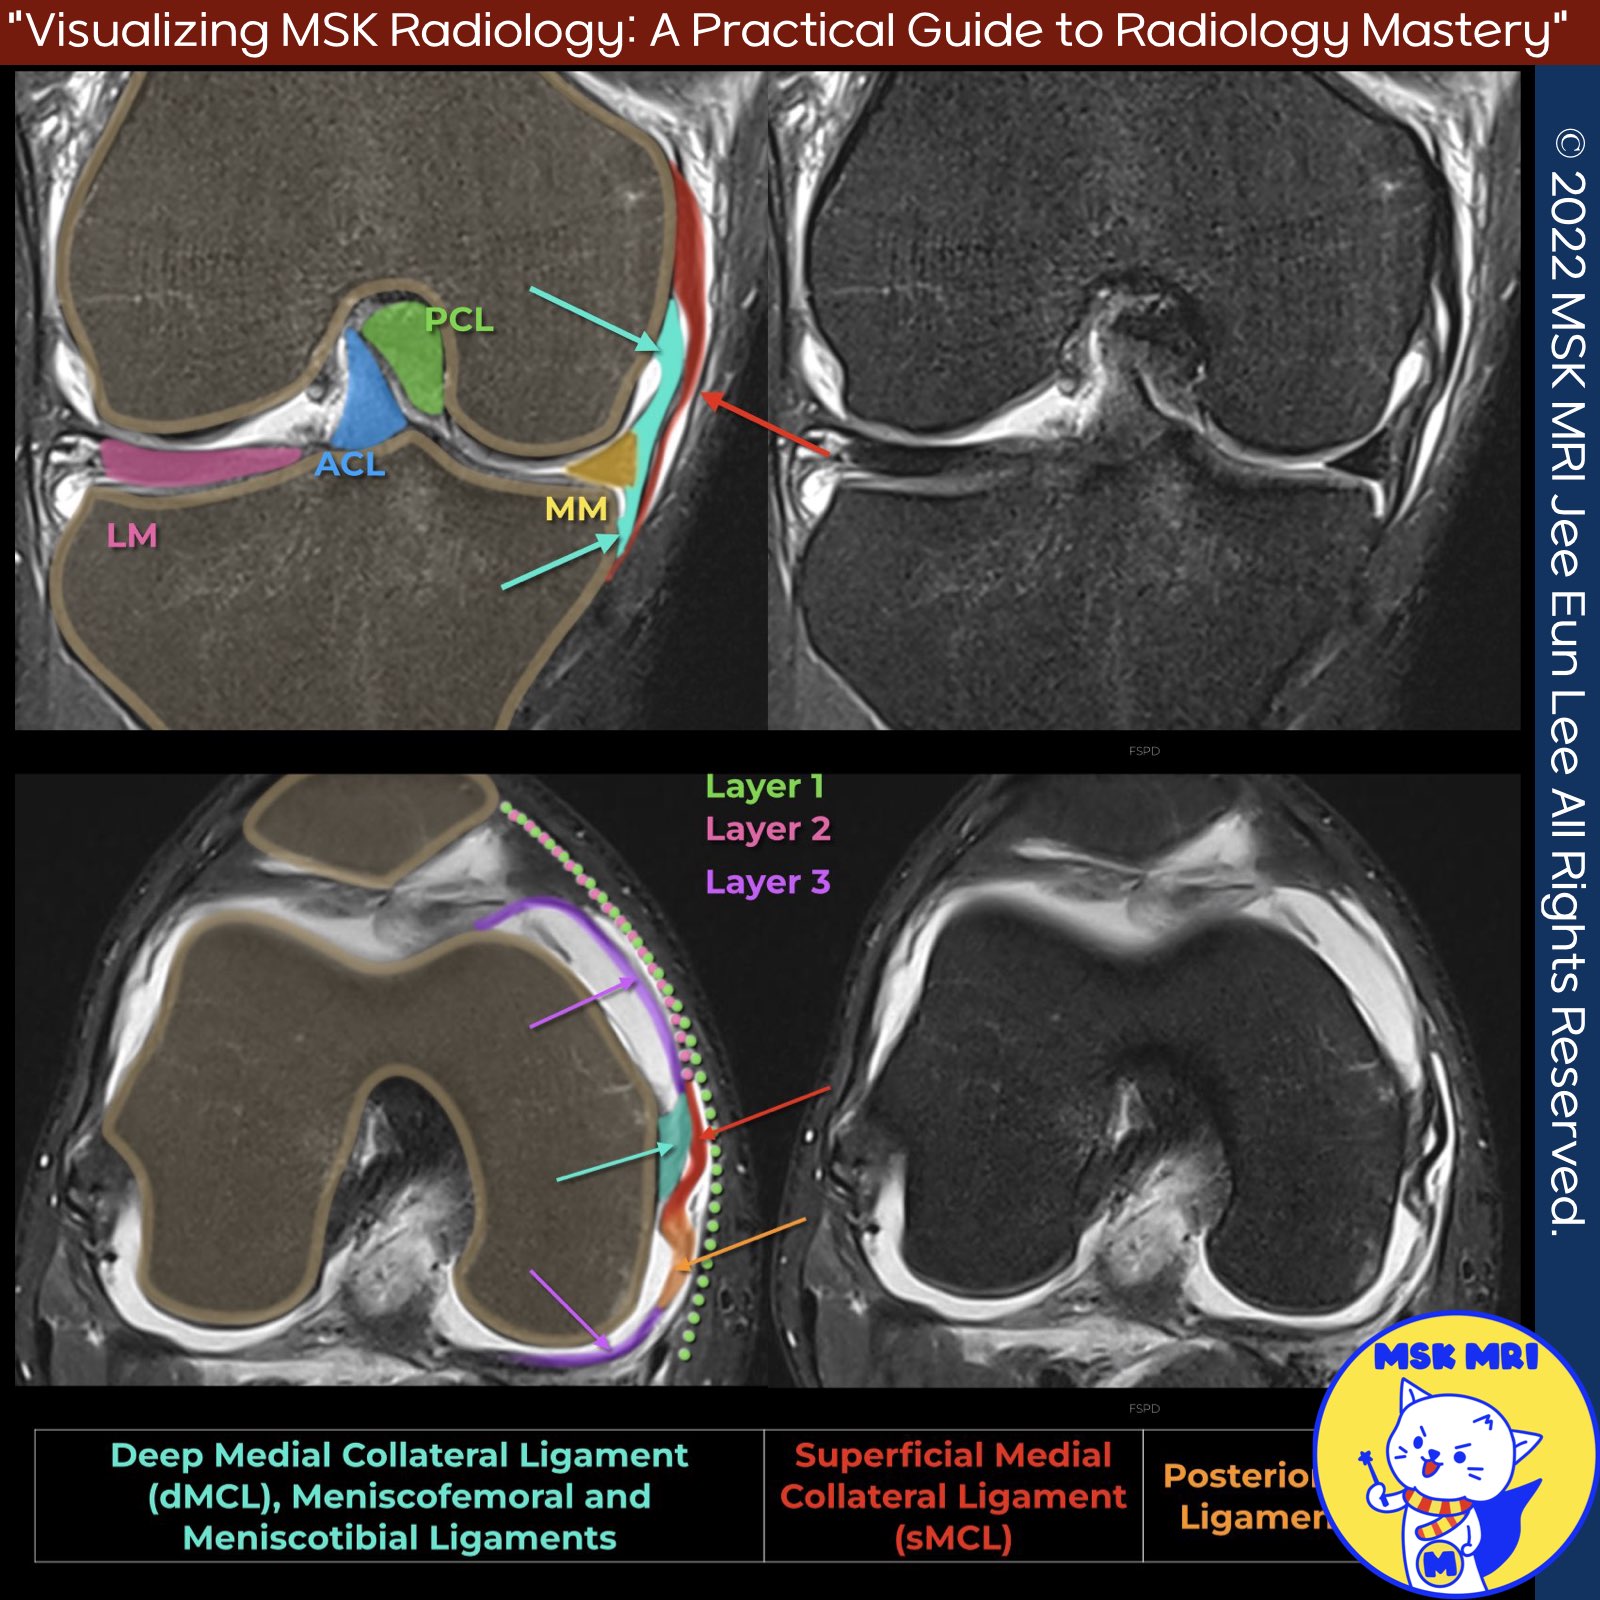

📌Deep Medial Collateral Ligament

- The deep medial collateral ligament (dMCL) is an essential independent stabilizer of the knee joint, adhering to the articular capsule.

- Rupture of the dMCL can clinically mimic a meniscal tear, highlighting the importance of recognizing and properly evaluating this structure during knee examinations and imaging studies.

✅Anatomy Orientation and Attachments

- Recent findings have revealed that the dMCL has a distinctive fan-shaped orientation, extending antero-distally towards a 22 mm wide tibial attachment located approximately 8 mm distal to the joint line.

- The dMCL is a thickening of the medial joint capsule.

- It has a broad, firm attachment to the midbody of the medial meniscus, situated between the meniscofemoral attachment of the posterior oblique ligament (POL) and the anteromedial capsule.

✅ Meniscofemoral ligament:

- Inserts at the meniscus' upper medial border

- Attaches to the medial femur just below the insertion of the superficial MCL (sMCL)

- May not be visible on MRI due to its proximity to the sMCL or femur

✅ Meniscotibial ligament:

- Inserts at the meniscus' lower medial border

- Has a short course to its attachment at the medial corner of the tibia, immediately below the joint line

In summary, the dMCL is a crucial independent stabilizer of the knee joint, with distinct attachments to the tibial plateau, medial meniscus, and associated meniscofemoral and meniscotibial ligaments. Its strategic location and connections underscore its significance in maintaining knee stability and proper function.